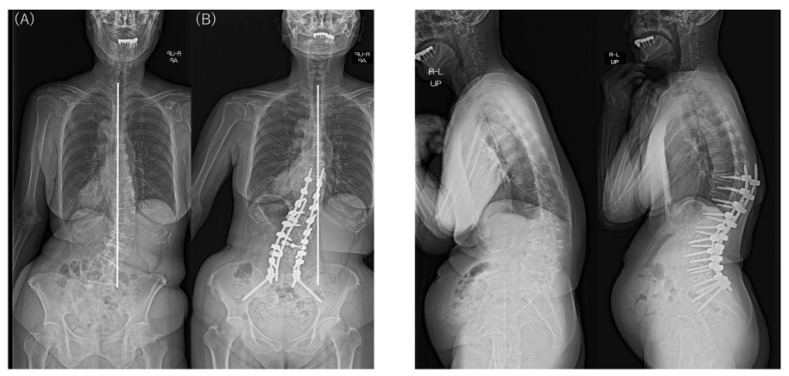

In the examination of the radiographic sagittal parameters across the entire cohort, we found significant improvements in PI–LL, including SVA, LL, and PT. However, TK and PJA increased postoperatively. The major Cobb angle was corrected markedly from 48.8° preoperatively to 13.2° postoperatively (p < 0.001). L4 coronal tilt improved significantly from 18.6° preoperatively to 8.7° postoperatively (p < 0.001) and L5 coronal tilt from 12.9° preoperatively to 7.3° postoperatively (p < 0.001). The major Cobb angle and L4 and L5 coronal tilts also improved in both groups. However, the L4 and L5 coronal tilt were larger before and after surgery in the Obeid type 2 group than in the Obeid type 1A group. The │CBD│ did not differ significantly between the type 1A and type 2A groups before and after surgery. In patients with Obeid type 1A, the │CBD│ changed from 78.4 mm before to 22.8 mm after surgery (p < 0.001). In patients with Obeid type 2A, the change in the │CBD│ from 46.9 mm to 38.5 mm was not significant (p = 0.506) (Table 3).

Analysis of the change or correction (Δ) for each spinal parameter showed a significant difference in ΔTK for the sagittal parameter TK. ΔTK was larger in patients with Obeid type 2A, but other sagittal parameters did not differ significantly between groups. Δ│CBD│ was significantly larger in patients with Obeid type 1A than those with Obeid type 2A (76.6 mm vs. 24.1 mm; p < 0.001) (Table 4).

There were no significant intergroup differences in the changes in the major Cobb angle, correction of coronal tilts of L4 and L5, and the PJA (Table 4). CM was found in 29 of 34 patients with SRS–Schwab type L ASD preoperatively and remained in 12 of these patients at the final follow-up. At the final follow-up, 58.6% (17/29) of patients with SRS–Schwab type L CM showed improvement in CM after corrective fusion using LLIF. Although the difference was not statistically significant, CM improved in 69.6% of patients with Obeid type 1A CM but only 16.7% of those with Obeid type 2A CM (p = 0.056) (Table 5).

Typical postoperative changes are shown in Figure 2, Figure 3 and Figure 4.

Therefore, we focused on whether the LLIF procedure with posterior fusion would change the radiological outcomes of CM correction. About half of our patients with ASD were classified as having type L using the SRS–Schwab system, and CM was found in 29 of these patients (85.3%). Most patients showed the Obeid type 1A curve pattern. By contrast, patients with Obeid type 2A showed a smaller ΔCBD postoperatively, and many still exhibited CM after surgery.

All patients received LLIF as the spinal correction surgery in this study. In the sagittal plane, it was suggested that CM types did not affect SRS–Schwab assessment factors ΔSVA, ΔPT, and ΔPI-LL. LLIF and posterior corrective fusion corrected the preoperative CM in nearly 70% of patients with Obeid type 1A. However, using LLIF to correct the CM deformity in the coronal plane in a patient with Obeid type 2A may worsen the main lumbar curve by causing malalignment toward the convex side (Figure 5 and Figure 6).

L4 tilt was larger before and after surgery in patients with Obeid type 2 CM than in those with Obeid type 1 CM, and there was no change in CBD before and after surgery in patients with Obeid type 2 CM.